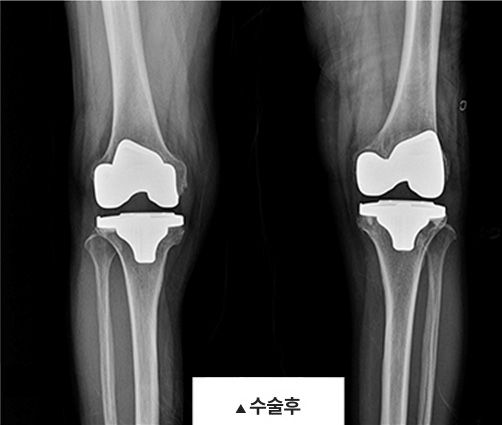

무릎 인공관절 치환술이란?

통증의 원인이 되는 손상된 연골을 인체공학적으로 제작된 연골로 대체해주는 수술로

심각한 퇴행성관절염으로 손상이 심한 뼈(관절면)을 제거하고 특수한

금속, 플라스틱으로 제작 된 ‘인공 관절’을 각각의 부위에 맞게 삽입하여 관절의 역할을

대체할 인공 관절을 만들어 주는 치료법입니다.

전치환술은 무릎의 내측, 외측, 앞쪽(슬개-대퇴 관절면)의 심한 퇴행성 변화가 있을 때 시행하며,

반치환술은 내측 또는 외측의 심한 관절염이 있는 경우에 시행합니다.